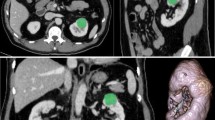

The study cohort comprised of 124 low-grade (17 were grade 1 (9.6%) and 107 were grade 2 (60.5%)) and 53 high-grade (40 were grade 3 (22.6%) and 13 were grade 4 (7.3%)) ccRCC patients who met the inclusion criteria (Table 1). The groups did not differ significantly with regard to age, sex, or lesion diameter (p > 0.05). Imaging and histological results from two representative patients are provided in Fig. 2.

Representative examples of clear cell renal cell carcinoma (ccRCC). a–e Low-grade (Fuhrman nuclear grade 2) ccRCC in a 49-year-old man. a–d Unenhanced phase (UP), corticomedullary phase (CMP), nephrographic phase (NP), and excretory phase (EP) CT images (red arrows point to the tumor in the left kidney). e Histologic photomicrograph (hematoxylin–eosin, H & E stain). f–j High-grade (Fuhrman nuclear grade 3) ccRCC in a 69-year-old man. f–i UP, CMP, NP, and EP CT images (red arrows point to the tumor in the right kidney). j H & E stain